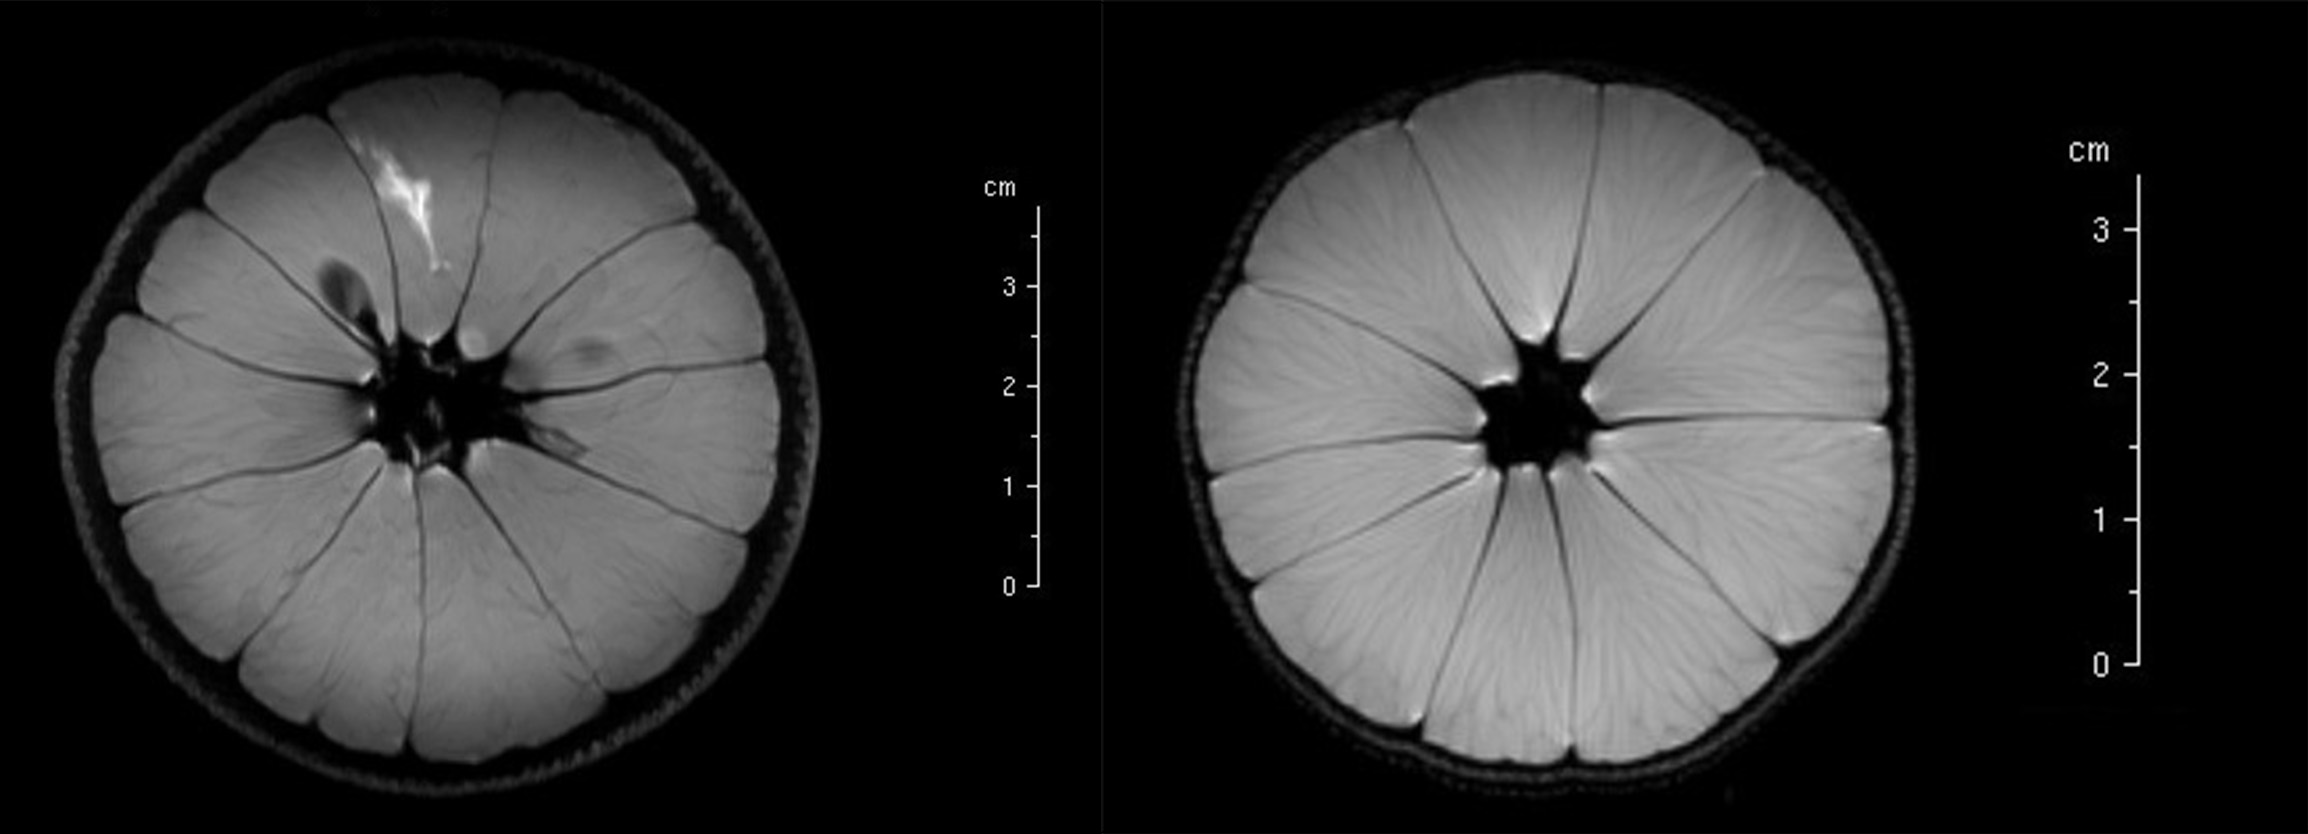

Figure 17: 1H MRI of an orange. Left: image obtained from a T1-based sequence; note the bright spot of intense signal intensity, caused by local injection of a contrast agent (see below). Right: image obtained from a T2-based sequence. Comparison of the two images illustrates subtle differences in the way how textures are depicted in different MRI sequences, depending on the differences in T1/T2 characteristics of a sample/tissue.

Figure 19: Summary of T1WI approaches. Left: basic sequence for obtaining T1-based images; right: T1-based image of an orange, the seed appears dark in the image because it is much more rigid and contains less water than the surrounding flesh of the fruit.

Figure 20: Summary of T2WI approaches. Left: basic sequence for obtaining T2-based images; right: T2-based image of an orange, the seed is invisible to this experiment but there is good natural contrast of the various (soft) components of the fruit segements.